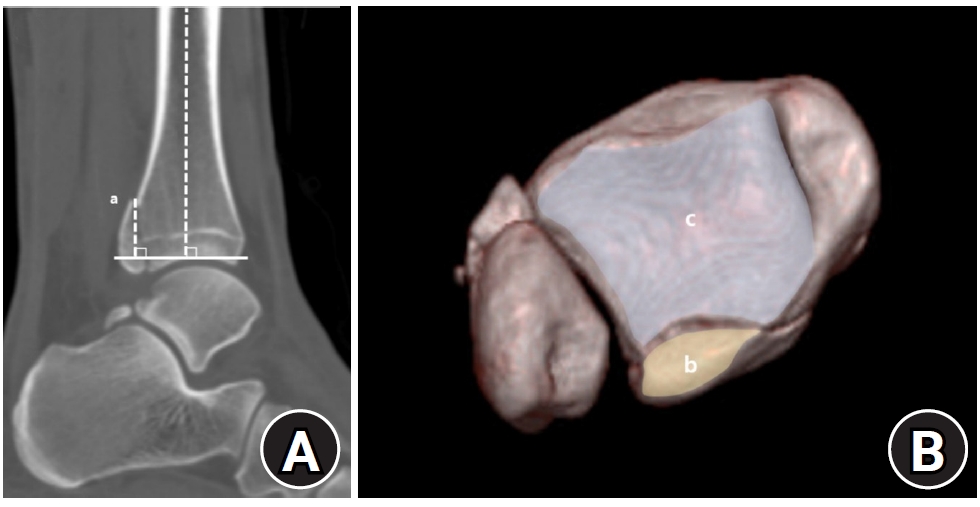

Demographic and clinical data were obtained from electronic medical records. Radiographic data were derived from 3D-CT scans. Radiographic analysis was performed using 3D-CT to assess the characteristics of both lateral and posterior malleolar fractures. Lateral malleolar fracture patterns were determined by measuring the vertical distance between the highest posterior cortex or lowest anterior cortex of the fracture and a line perpendicular to the tibial axis at the distal tibial articular surface. The angle between the posterior cortex of the lateral malleolus and the line connecting the anterior and posterior cortical points was defined as the fracture angle (Fig. 1).

Fig. 1.

Radiographic assessment of fracture characteristics. (A) Posterior height (a) and anterior height (b) represent the vertical distances from the highest point of the posterior cortex (▼) and the lowest point of the anterior cortex (▲) of the distal lateral fibula, respectively, to the line perpendicular to the tibial axis that intersects the distal tibial articular plafond. (B) The fracture angle (c) of the lateral malleolar fragment is defined as the angle between the posterior cortex of the lateral malleolus and the line connecting the anterior and posterior cortical points of the fracture.